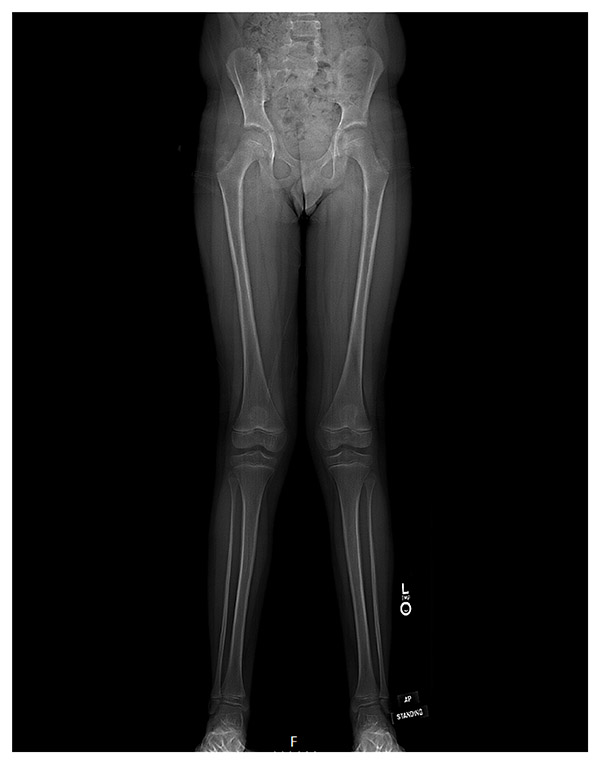

Following a patellar dislocation of the left knee, a 9-year-old skeletally immature boy was diagnosed with genu valgum accompanied by recurrent bilateral patellar instability. His right knee was significantly less symptomatic. Bilateral X-rays and long-standing EOS radiographs demonstrated bilateral genu valgum and lateral patellar subluxation, with increased patellar tilt also noted (Figure 1). On clinical examination, there was patellar apprehension, full range of motion, and mild J-sign bilaterally.

Figure 1: Preoperative EOS radiograph of 9-year-old boy demonstrating bilateral genu valgum.